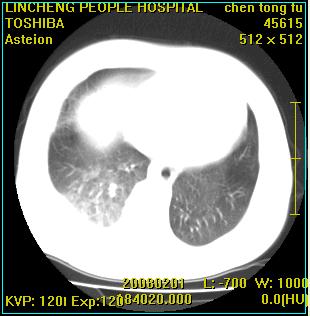

标题: CT11942:男性,62岁。右肺的病变 [打印本页]

患者,男性,62岁。主因头晕,发热,咳嗽6天,高热达39度,esr19mm/h,wbc 3.9×10 9/l

大叶性肺炎并胸膜炎

实变区见空气支气管征,支气管通畅,考虑为大叶性肺炎,右侧少量胸水

大叶性肺炎并胸膜炎、胸水。

右侧大叶性肺炎,右侧少量胸腔积液.

实变区见空气支气管征,支气管通畅,考虑为大叶性肺炎,右侧少量胸水。